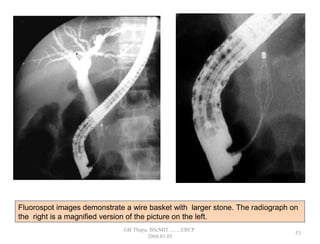

Fluorospot images demonstrate a wire basket with larger stone. The radiograph on

the right is a magnified version of the picture on the left.

• 48.

Fluorospot images demonstratea wire basket with larger stone. The radiograph on the right is a magnified version of the picture on the left. 53 GB Thapa, BScMIT.........ERCP 2068.01.05